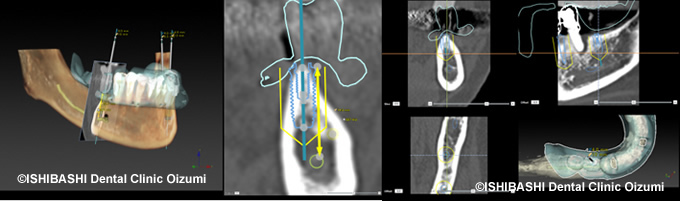

当院では、インプラント治療の前にCTデータをシミュレーションソフト『ノーベルクリニシャン』へと取り込み、患者さんの顎骨の状態や骨質を精密に診断した上で、使用するインプラントの種類や径、長さ、角度などを決定していきます。このコンピュータシミュレーションによってインプラント治療をより正確に施術することを目指します。

当院では、ノーベルバイオケア社の『ノーベルクリニシャン』インプラントシステムを使用し、CTデータによる正確な診断、設計を行っています。

『ノーベルクリニシャン』とは、『インプラント療法をより正確にサポートし、治療を行う為のシステム』です。

まず、CTスキャンにより患者様の顎骨の形を完全に再現した3D情報を使用します。

これにより、事前に『インプラントを埋入するための十分な骨があるか』『どの角度で、太さ何ミリのインプラントを、深さ何ミリまで入れれば良いか』といった、事前の情報が分かります。

また、この情報を元に綿密な手術計画が立てられるので、普通のインプラント治療よりも手術にかかる時間が少なくなります。

そして、計画が綿密であるため、手術の前に患者様にしっかりとしたご説明ができ、手術をお受けいただけます。